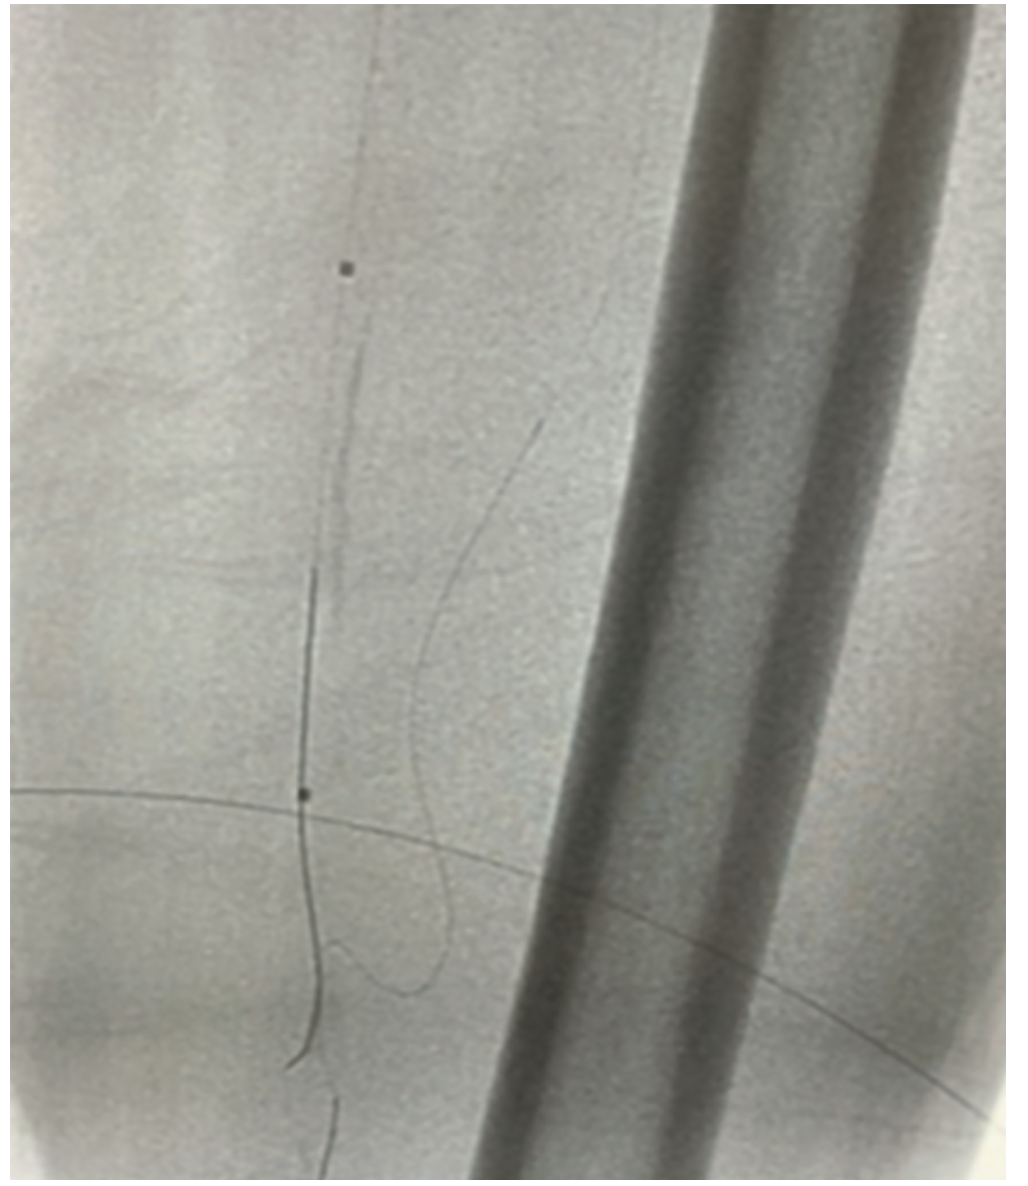

Following the diagnostic angiogram, we initially upsized to a 6 French 45 cm sheath (Cook Medical) and an .035-inch 260 cm Zip wire (Boston Scientific) did take the initial channel of the SFA. An .035-inch Rubicon microcatheter (Boston Scientific) was advanced and the wire was switched out to a Gladius .018-inch (Asahi Intecc). The knuckle was advanced distally, but did not re-enter at the reconstitution point. There was some diffuse disease distal to the reconstitution point and the goal was to not extend the dissection plane. Initial attempts were made to redirect with an .014-inch Halberd (Asahi Intecc) and penetrate the cap that way; however, it deflected off the distal cap. Pedal access was considered, but had an initial difficult access secondary to poor imaging and patient cooperation. After reviewing the films, it appeared there was path from a collateral off the profunda. The Halberd .014-inch wire was left in place as a marker wire. A Sion Black (Asahi Intecc) and a secondary microcatheter were advanced through the profunda and into the collateral. The wire was advanced through and came in right at the distal cap. Although we could not get enough purchase retrograde to advance a retrograde knuckle, the retrograde wire was able to manipulate the distal cap and caused some plaque modification (Figure 2). At that point, the antegrade Halberd wire was able to be redirected, entered the vessel at the reconstitution point, and wired distally. The .035-inch Rubicon microcatheter was advanced and switched out for a Sion Black. A 2.0 Auryon laser (AngioDynamics) with aspiration was used to performed laser atherectomy with <50 mL of aspirate (Figure 3). Total lesion length was approximately 220 mm. After about 2 minutes of treatment at 50 mmJ2, intravascular ultrasound (IVUS) (Boston Scientific) was performed, demonstrating a dissection distally at the cap. On pullback, there was diffuse plaque in the vessel but it was luminal (the proximal one-third of the vessel). Therefore, the plan was to treat the distal part of the lesion with a stent (to seal the dissection) and perform percutaneous transluminal angioplasty (after the laser) of the proximal vessel. After IVUS, we took a 5.0 mm x 200 mm Charger balloon (Boston Scientific), and inflated distally at 6 atmospheres and then to 10 atmospheres, and we came in proximal in the SFA. There was now reconstituted flow. The lesion distal to the reconstitution point was touched up with low-pressure balloon inflation, and then, based on the dissection plane, a 6 mm x 150 mm stent was placed. We did some post dilatation, and brisk flow to the SFA and no evidence of distal embolization were seen following angiography (Figure 4). The patient tolerated the procedure well. The wire was removed and repeat angiography demonstrated the same status: no dissection, perforation, or embolization.